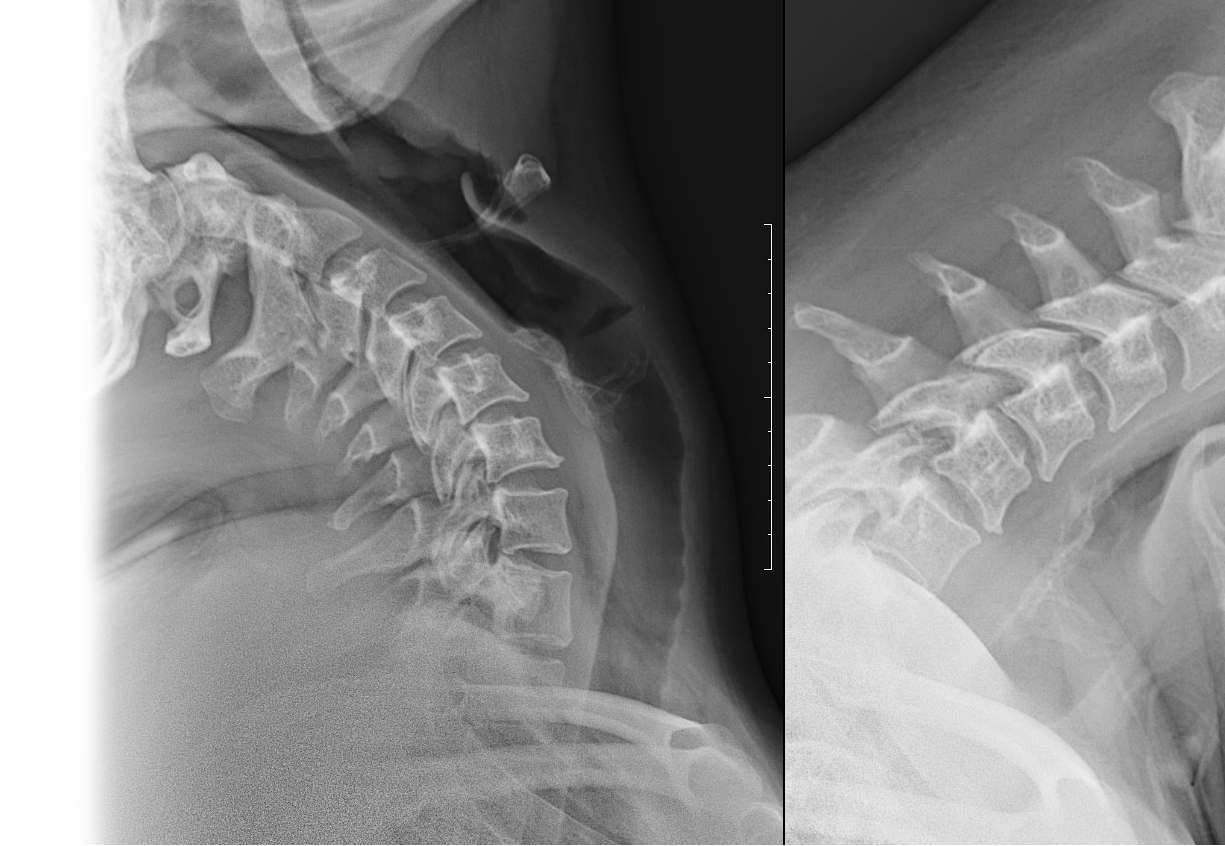

Рентгенография одного отдела позвоночника: функциональные пробы Рентгенография одного отдела позвоночника: функциональные пробы

Рентгенография одного отдела позвоночника: функциональные пробы – важный метод скринингового исследования, который позволяет оценить состояние отдела позвоночника.

• дискомфорт в позвоночнике, усиливающийся при наклонах и поворотах;

• оценка подвижности позвонков, их патологическое смещение.